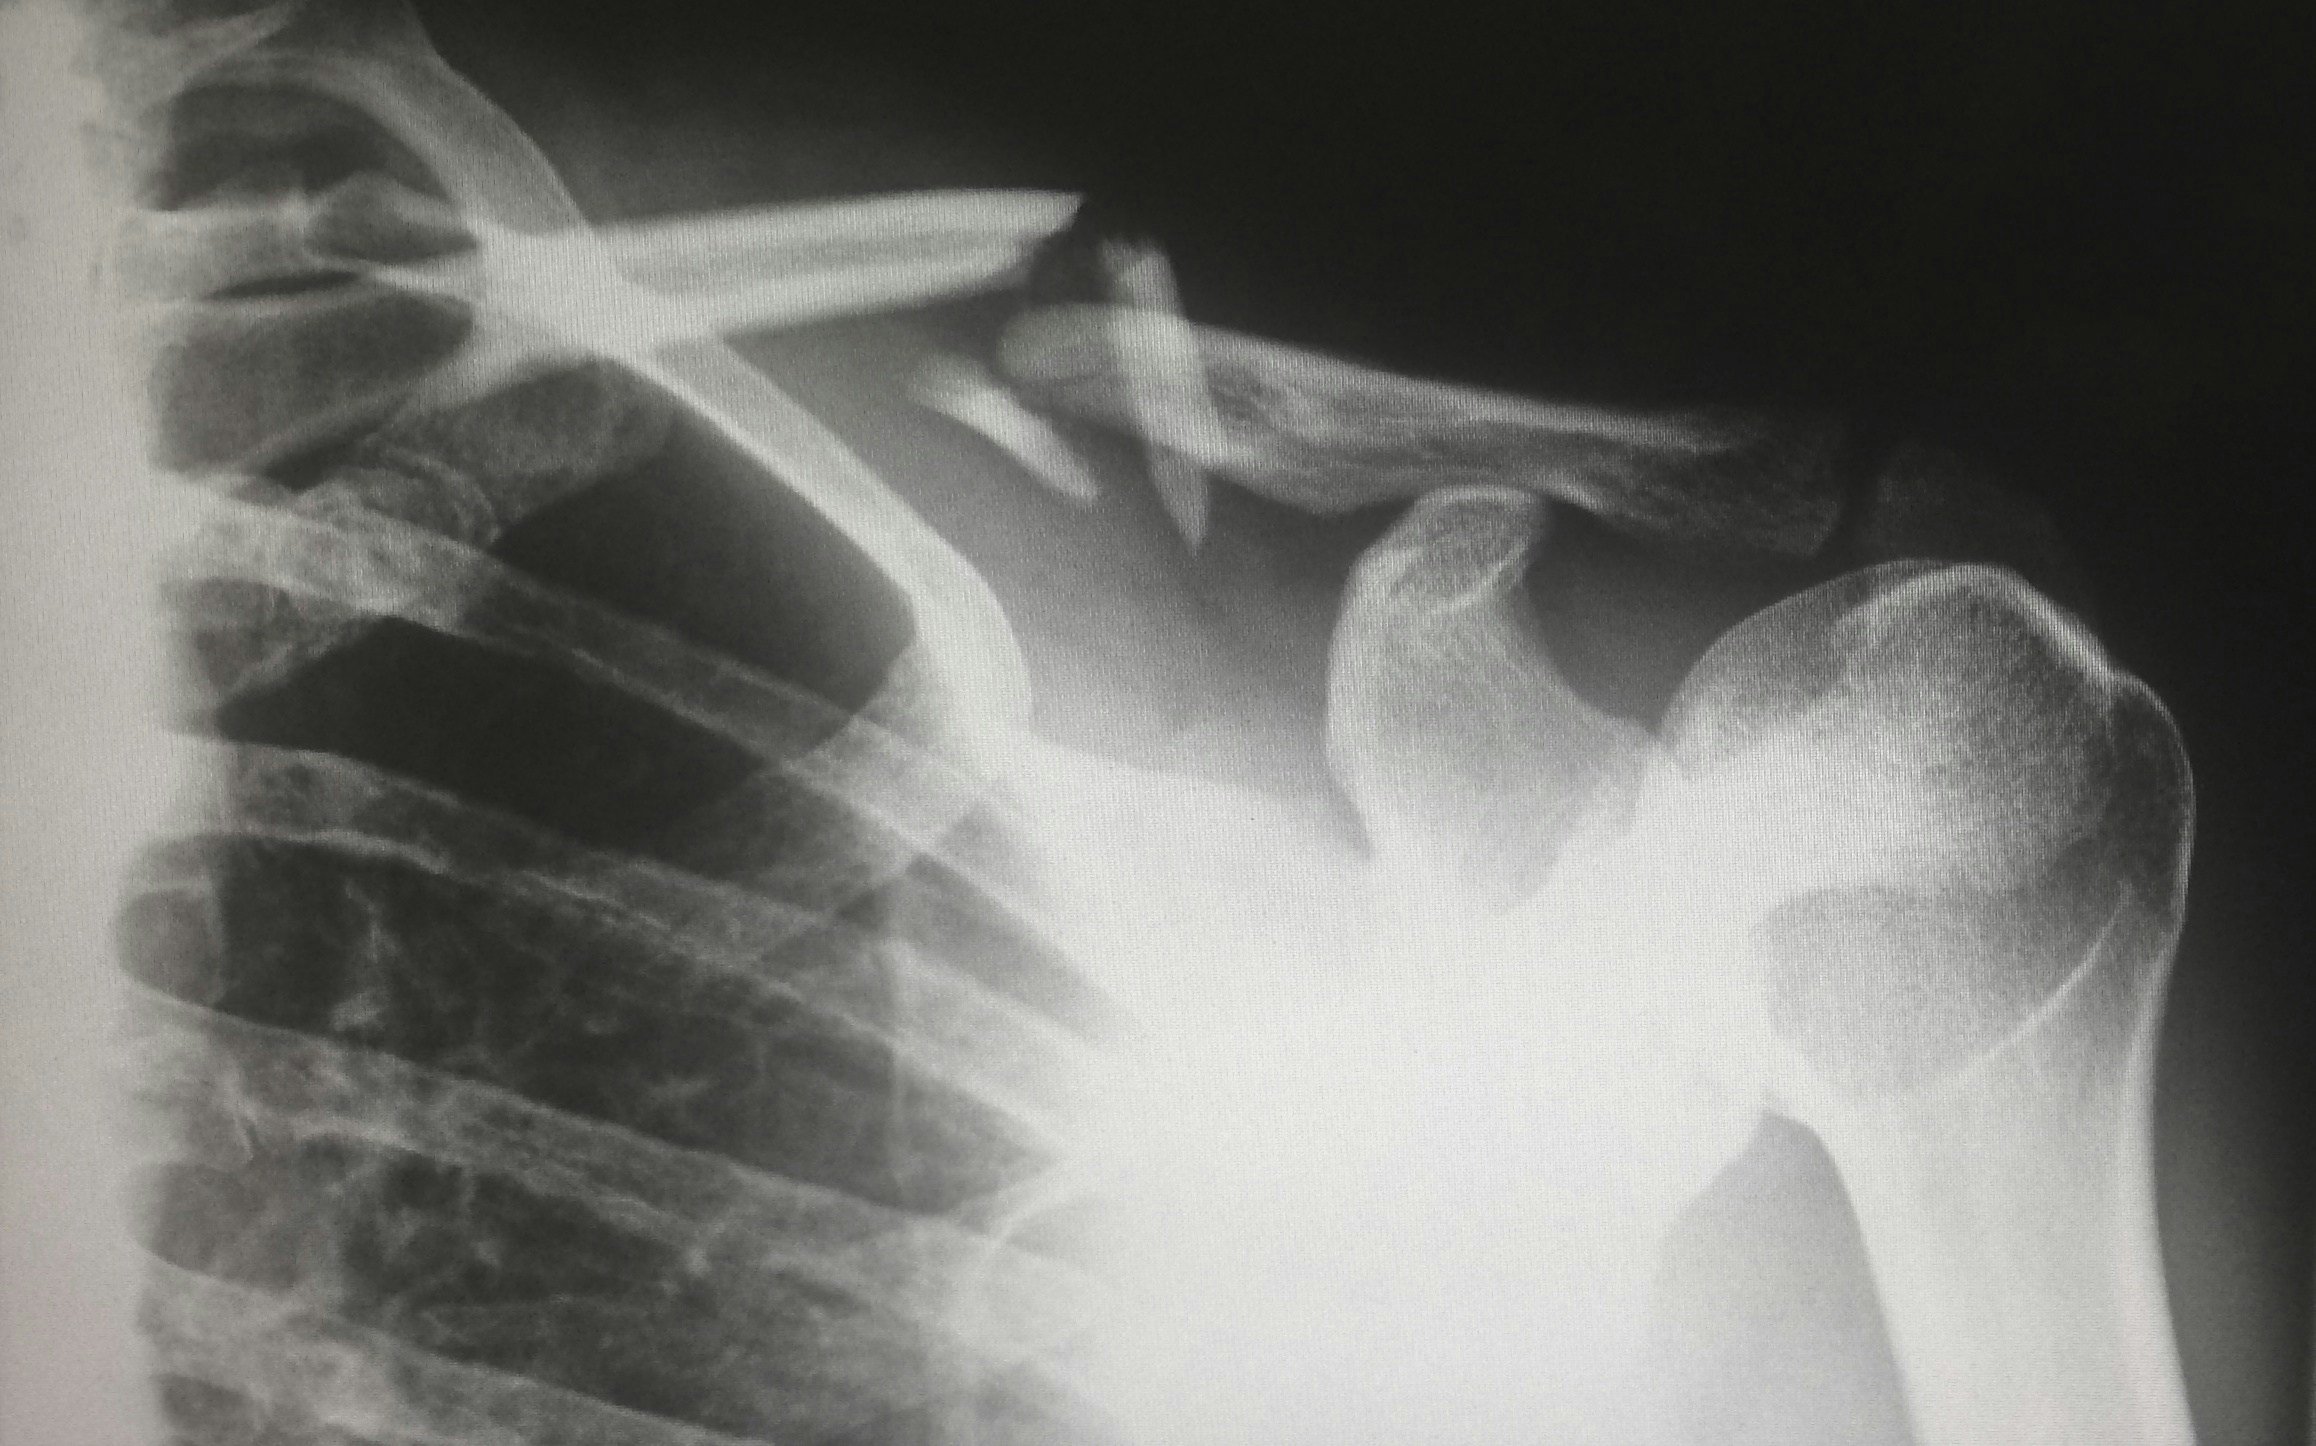

인공관절 클리닉

모세정형외과의 인공관절 클리닉은 최첨단 장비와 최신 의료기술로 전문적으로 진단하고 환자의 상태에 따라 맞춤형 치료 방법을 제공합니다.